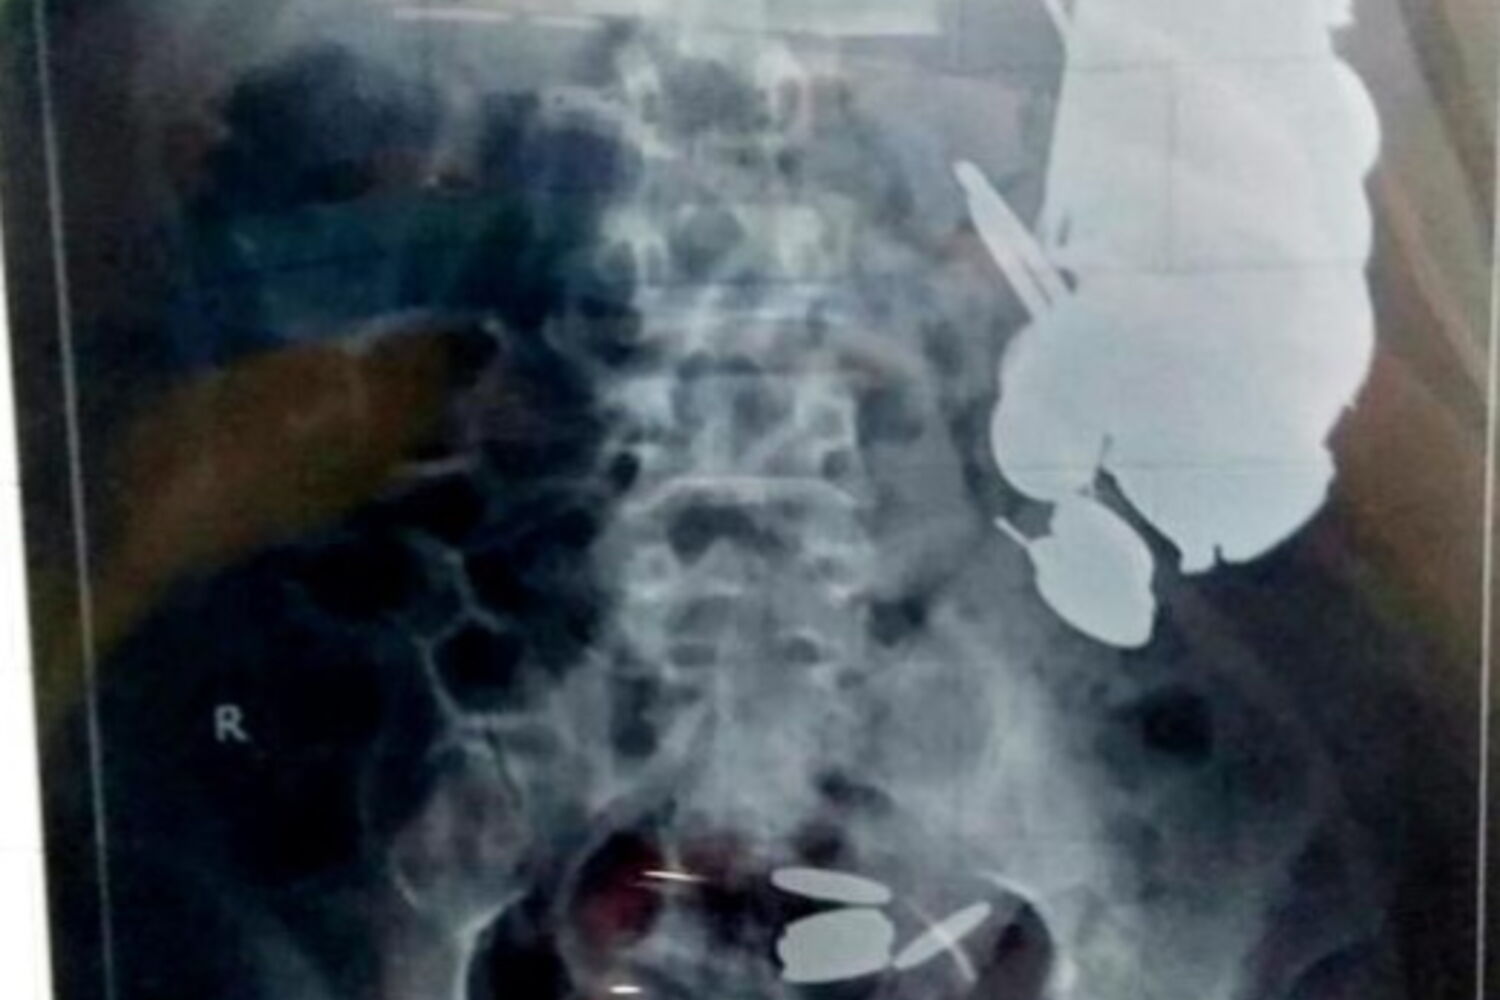

Um homem indiano que deu entrada no hospital devido a dores abdominais tinha centenas de agulhas e moedas no seu estômago. A descoberta macabra foi feita durante uma endoscopia e Maksud Khan, de 35 anos, foi prontamente operado.

Os médicos fizeram o exame e nada faria prever que estas seriam causadas por cerca de 7 quilos de objetos. "Foi o primeiro caso semelhante em toda a minha carreira", afirmou o cirurgião Priyank Sharma, um dos que operou Khan.O indiano tinha 1,5 quilos apenas em agulhas, bem como mais de duas centenas de moedas, lâminas e alguns pedaços de vidro no estômago. Foi operado e os objetos removidos. Está fora de perigo.